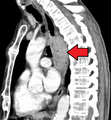

Additional testing is needed to assess how much the cancer has spread (see #Staging, below). Computed tomography (CT) of the chest, abdomen and pelvis can evaluate whether the cancer has spread to adjacent tissues or distant organs (especially liver and lymph nodes). The sensitivity of a CT scan is limited by its ability to detect masses (e.g. enlarged lymph nodes or involved organs) generally larger than 1 cm. Positron emission tomography is also used to estimate the extent of the disease and is regarded as more precise than CT alone. Esophageal endoscopic ultrasound can provide staging information regarding the level of tumor invasion, and possible spread to regional lymph nodes.

Contrast CT scan showing an esophageal tumor (axial view)

Contrast CT scan showing an esophageal tumor (coronal view)